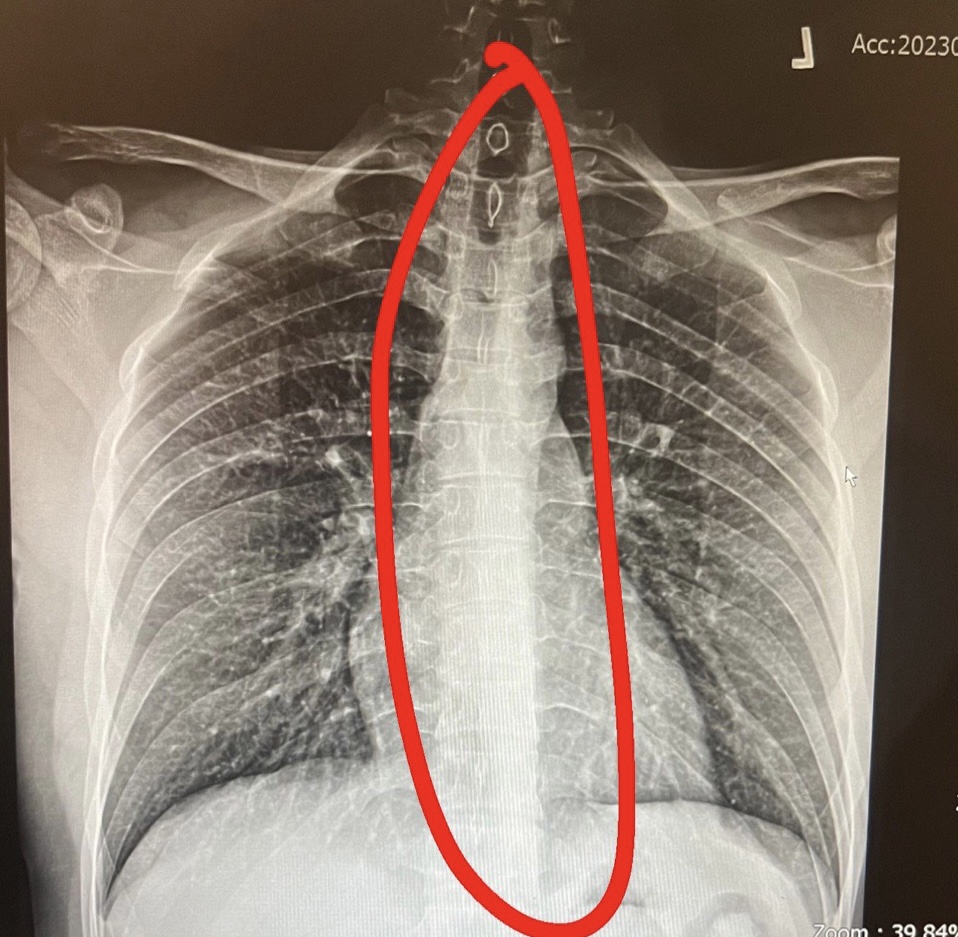

แบบนี้กระดูกสันหลังคดไหมครับ

แบบนี้กระดูกสันหลังคดรึเปล่าครับ

แบบนี้กระดูกสันหลังคดไหมครับ แล้วถ้าคดประมาณกี่องศา